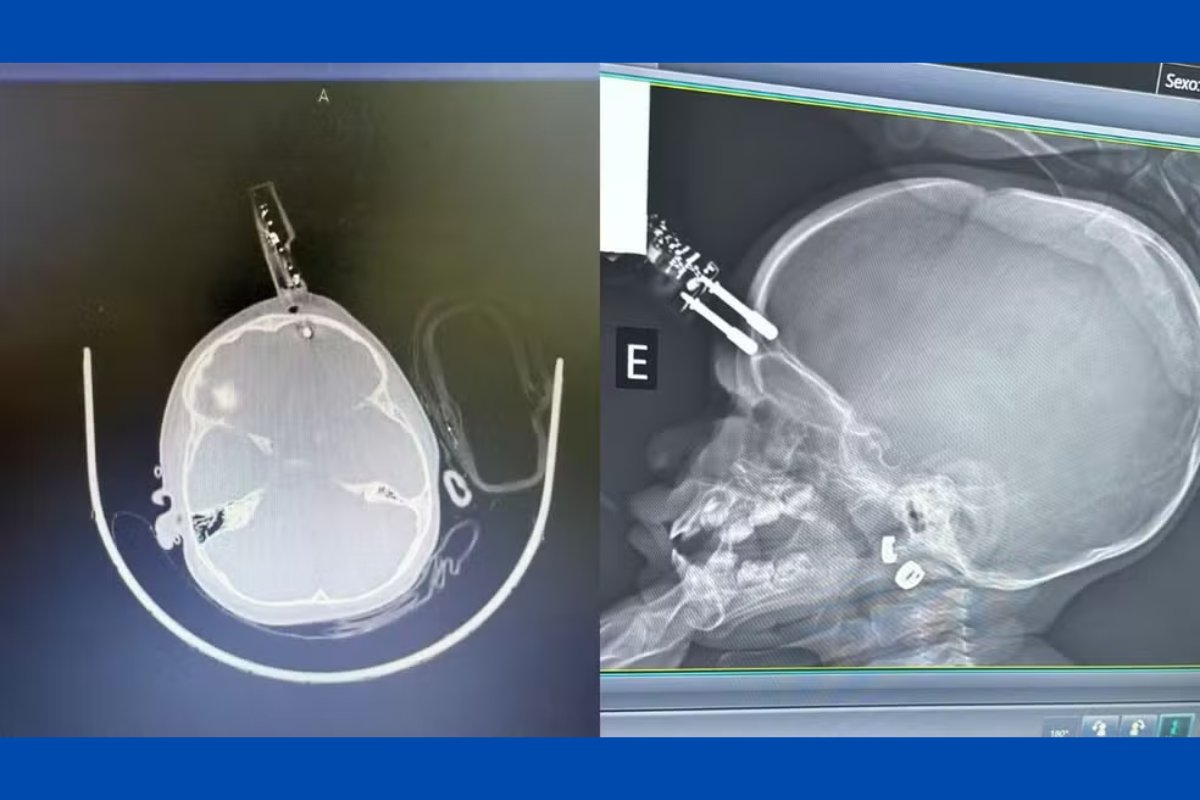

Uma menina de 1 ano sofreu um acidente doméstico, na última terça-feira (13), e ficou com um carregador de celular cravado na testa após cair da cama da residência onde mora, em Divinópolis, em Minas Gerais.  [Veja foto ao final da matéria]

A principal hipótese é que a menina estava com o carregador na mão quando caiu da cama e o objeto atingiu a cabeça de forma que perfurou a região frontal do crânio, próximo ao olho. A mãe da criança relatou que não viu o momento da queda da criança, pois havia ido ao banheiro.

Não foram divulgadas informações sobre o local em que a criança foi socorrida. O médico responsável pelo atendimento, o neurocirurgião Bruno Castro, informou que ela foi levada imediatamente ao bloco cirúrgico, onde passou por procedimentos de limpeza, retirada do objeto, lavagem, fechamento e reconstrução da área atingida.

A menina segue internada e recebe antibiótico profilático, segundo protocolo médico. O neurocirurgião, a capacidade de recuperação do cérebro infantil pode explicar a ausência de sinais de sequelas neurológicas até o momento.

Especialista alerta que lesões cerebrais podem gerar cicatrizes no cérebro, que podem desencadear crises convulsivas e epilepsia no futuro. Por isso, a criança deverá passar por acompanhamento neurológico contínuo.